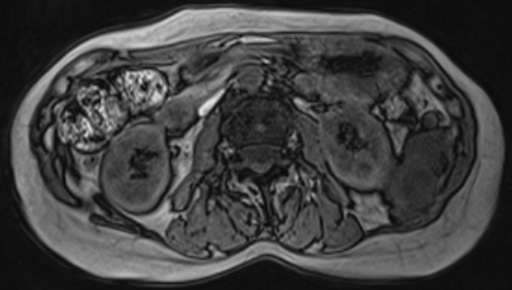

(右腎上極レベル) 図2 腹部造影CT

図2 腹部造影CT

(左腎門部レベル) 図3 左:T1強調横断像